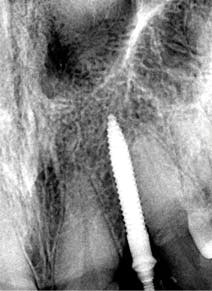

A 1.8 mm x 14 mm Anew implant (Dentatus) was selected, and a surgical guide was fabricated for a flapless approach. In this instance, a healing cap was placed, and the existing flipper was relieved to address financial concerns (figures 9 and 10). A screw-retained crown was fabricated three months post insertion (figures 11 and 12). The patient reported no postoperative discomfort, and the case remains successful, as shown in the two-year postoperative x-ray (figure 13).

Figure 9: Implant placement

Figure 13: Two-year follow-up